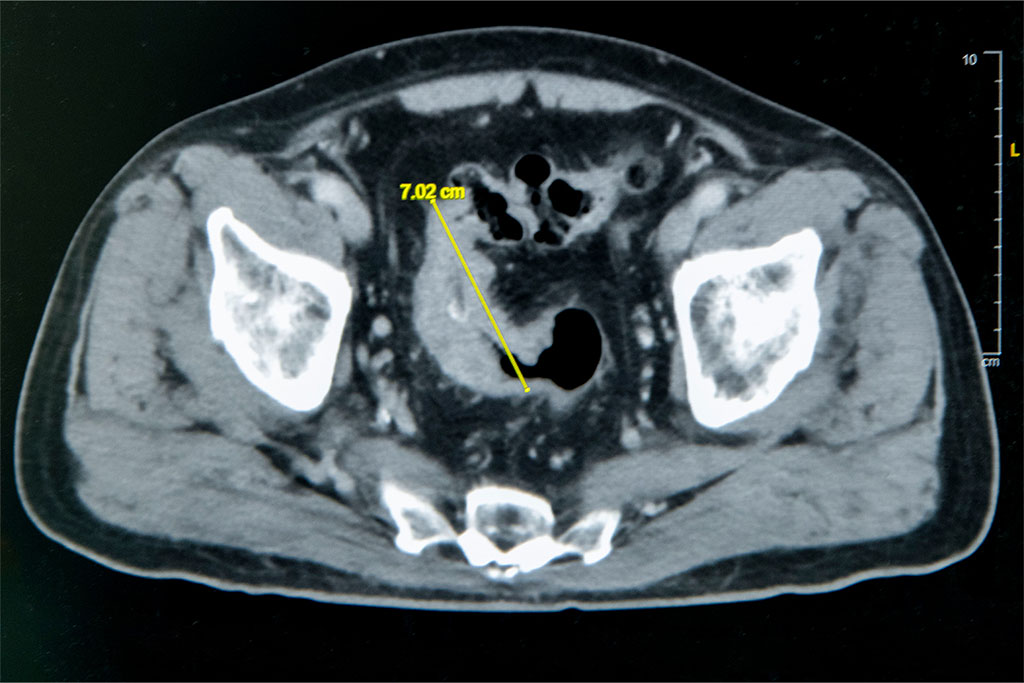

大腸直腸外科主任張譽耀醫師表示,老翁罹患乙狀結腸癌,腫瘤約7公分造成腸子幾乎完全阻塞,也導致老翁一進食就會肚子又脹又痛;術前因為不敢進食,老翁體重下降、營養不足,也可能造成傷口癒合不良。老翁的手術其實會有兩個傷口,一個是肚子上的傷口、一個腸子的傷口,若腸子傷口癒合不良會造成腸吻合滲漏,到時就必須做人工肛門了!所幸經過提早住院,透過靜脈營養針先建立營養,讓病人強健身體後才手術,術後傷口果然順利癒合。手術順利完成,老翁術後恢復良好,疼痛程度遠低於預期,他開心表示:「沒想到這麼快就能下床,真的很感謝醫師。」

老翁罹患乙狀結腸癌,腫瘤約7公分造成腸子幾乎完全阻塞。